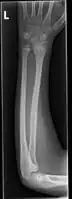

| Midshaft fracture of the radius and ulna | |

Front view of displaced fractured radius and ulna at wrist -

Side view of displaced fractured radius and ulna at wrist -